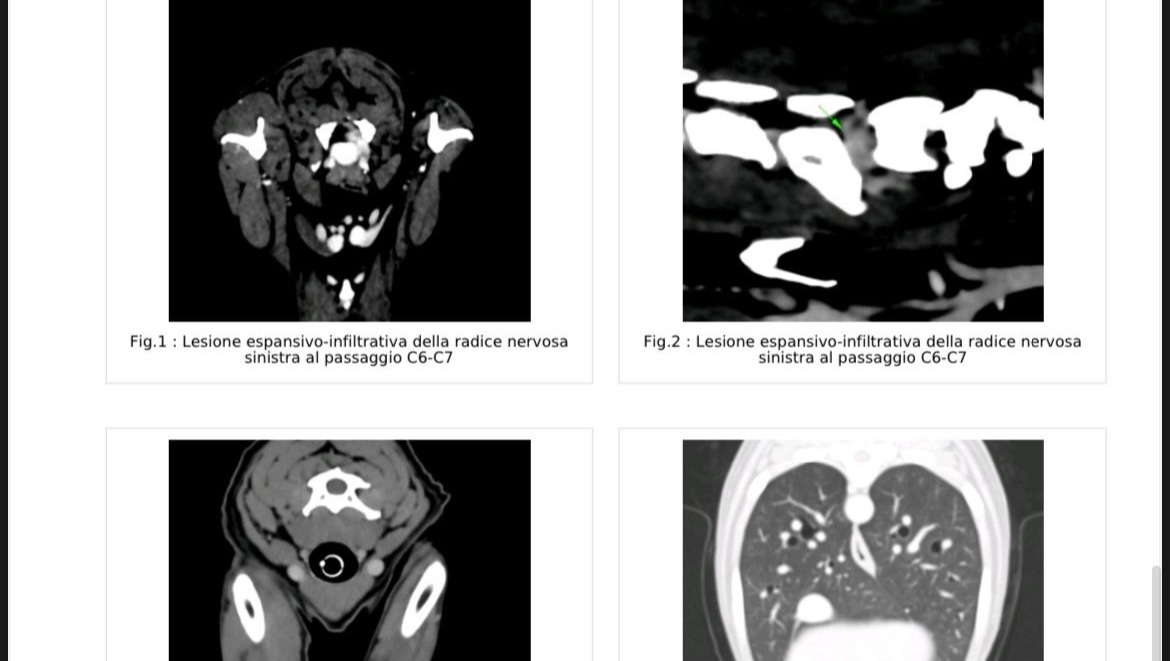

ITA: Joey, il nostro piccolo Fox Terrier di nove anni, con la sua gioia di vivere ha illuminato la nostra vita da quando è parte della nostra famiglia.Qualche mese fa si è improvvisamente manifestata una dolorosa zoppia ad un arto che in pochissimi giorni è divenuta paralisi. Il frenetico tentativo di individuare quale fosse la causa attraverso radiografia, TAC e risonanza magnetica ha portato alla terribile scoperta di un tumore alla radice dei nervi. Eravamo e tuttora siamo devastati. Il 4 febbraio scorso Joey è stato sottoposto ad un delicato intervento chirurgico per asportare la massa tumorale. Joey sta lottando per guarire nonostante la sofferenza e la difficoltà di movimento. Sfortunatamente la sua incredibile forza d'animo e il commovente desiderio di vivere non sono sufficienti: la biopsia ha diagnosticato poche possibilità di una totale guarigione. La radioterapia potrebbe aiutare ma è estremamente costosa. Inoltre la clinica specializzata si trova in Slovenia, ciò vuol dire fronteggiare anche i costi del viaggio e della permanenza. Saremmo veramente grati a chiunque volesse sostenerci con una donazione. Non importa quanto generosa. Insieme daremmo a Joey la speranza di vincere la sua battaglia.Finora non abbiamo risparmiato alcuno sforzo per aiutarlo e non desideriamo desistere ma senza il vostro supporto sarà difficile non arrendersi.

ENGL: Joey, our little nine year old Fox Terrier, has brightned up our life with his liveliness since he entered our family. Few months ago a painful lameness appeared and within a few days Joey showed paralysis of a front leg. The frantic attempt to identify the problem through X-rays, computer tomography and magnetic resonance led to the scary diagnosis of a nerve root tumor. We were, and still are, heartbroken. On February 4th Joey has undergone surgical removal. Since then, despite the pain and difficulty moving, Joey has been struggling hard to recover. Unfortunately, his amazing strong will and moving desire to live are not enough: the biopsy of the tumor diagnoses few chances for total recover. Radiation therapy may help but it is expensive. In addition, the clinic specialised is located in Slovenia which means that further expenses for travel and accomodation will follow. We would be really grateful to anyone who could support us with a donation, no matter how generous this might be. All together we can give Joey the chance to win his battle. We have spared no effort so far to help him and we don't want to surrender but without your help it might turn out to be really hard not to give up.